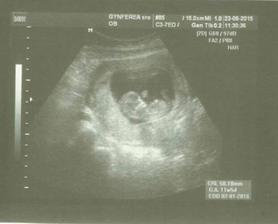

@lenkato7 áno od 20. 5. keď bilo srdiečko to je potvrdené a radujem sa najviac na svete 🙂 ďakujem a dúfam že sa čoskoro pridáš ♥